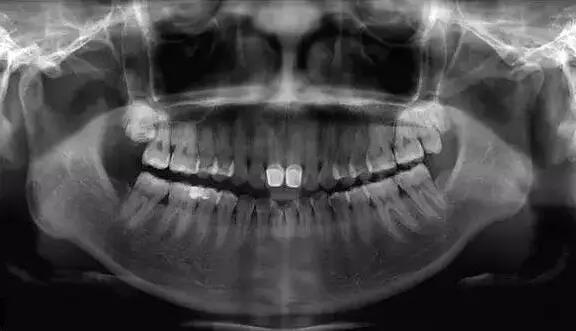

全口曲面断层片

看似复杂,用人话说就是口腔牙齿的X光片。

牙医通过对这张片的分析,能找出潜藏的牙周疾病问题、牙根发育等情况。通常是否拔牙、拔哪个牙、怎么拔,就是靠它了!